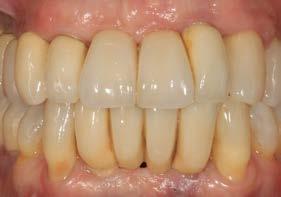

Una vez finalizados los postes, se prueban antes del cementado de las coronas para verificar que la zona ceramizada genere un margen gingival estético, evitando la exposición de metal incluso ante una posible recesión gingival leve. Asimismo, el hombro de la restauración se sitúa a nivel yuxtagingival, con el fin de evitar la presencia de cemento subgingival durante el cementado. Posteriormente se realiza la prueba de coronas (Figura 9) y su colocación definitiva (Figuras 10–12).

En una visión ampliada de la zona anterosuperior se aprecia la adecuada adaptación de los tejidos blandos a las coronas, lograda mediante la provisionalización y el diseño de pónticos y pilares que favorecen un contorno gingival armónico (Figuras 13 y 15).

Figuras 10 y 11. Prótesis definitiva colocada en la paciente.

La paciente continúa bajo seguimiento periodontal. A los 5 años se observa estabilidad clínica del tratamiento (Figuras 22–24), sin recesiones gingivales ni pérdida ósea asociada en las imágenes clínicas y radiográficas.

Un año más tarde, al finalizar el periodo de seguimiento (24 años), las fotografías intraorales evidenciaron ligeras alteraciones de los tejidos blandos, con pequeñas troneras abiertas,

más evidentes en los dientes naturales conservados que en las restauraciones implantosoportadas. A pesar de estos cambios, el resultado global se consideró satisfactorio desde el punto de vista funcional y estético, especialmente en comparación con la situación clínica y radiográfica inicial previa al tratamiento (Figuras 26–31).

Figuras 26–29. Imágenes clínicas a los 25 años. Se aprecia mínima pérdida ósea en dientes e implantes, con ligera apertura de troneras. Considerando el antecedente periodontal de la paciente, estos cambios pueden considerarse compatibles con una evolución controlada bajo mantenimiento estricto.

Figuras 30 y 31. Comparativa inicial y final a los 25 años de seguimiento, que muestra la estabilidad alcanzada tanto en los dientes conservados como en los implantes.